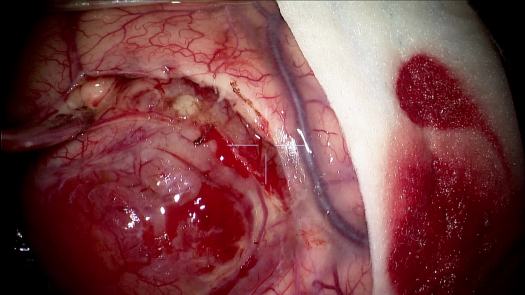

Resezione microchirurgica di tumore cerebrale (glioma alto grado cortico-sottocorticale) frontale dx